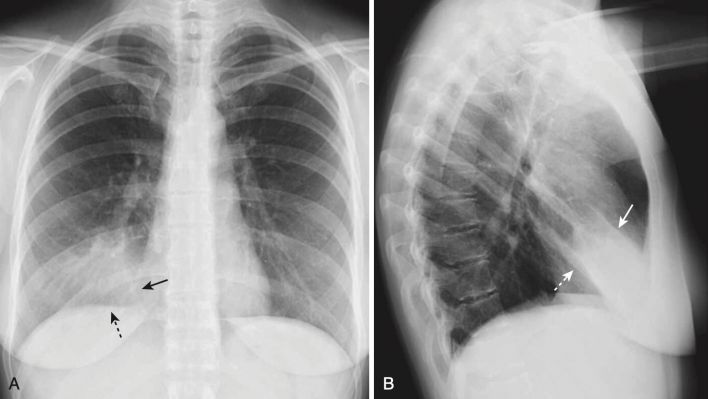

- Bệnh khoang chứa khí có thể biểu hiện dấu bóng bờ (dấu xoá bờ – silhouette sign) (Hình 4).

- Dấu xoá bờ xảy ra khi hai cấu trúc có cùng mật độ X quang (chẳng hạn như nước và mô mềm) chạm vào nhau sao cho rìa hoặc bờ giữa chúng biến mất. Không thể nói cấu trúc này này bắt đầu ở đâu và cấu trúc kia kết thúc ở đâu. Dấu hiệu bóng bờ không chỉ có giá trị ở ngực mà còn hỗ trợ cho việc phân tích các nghiên cứu hình ảnh ở những vị trí khác.